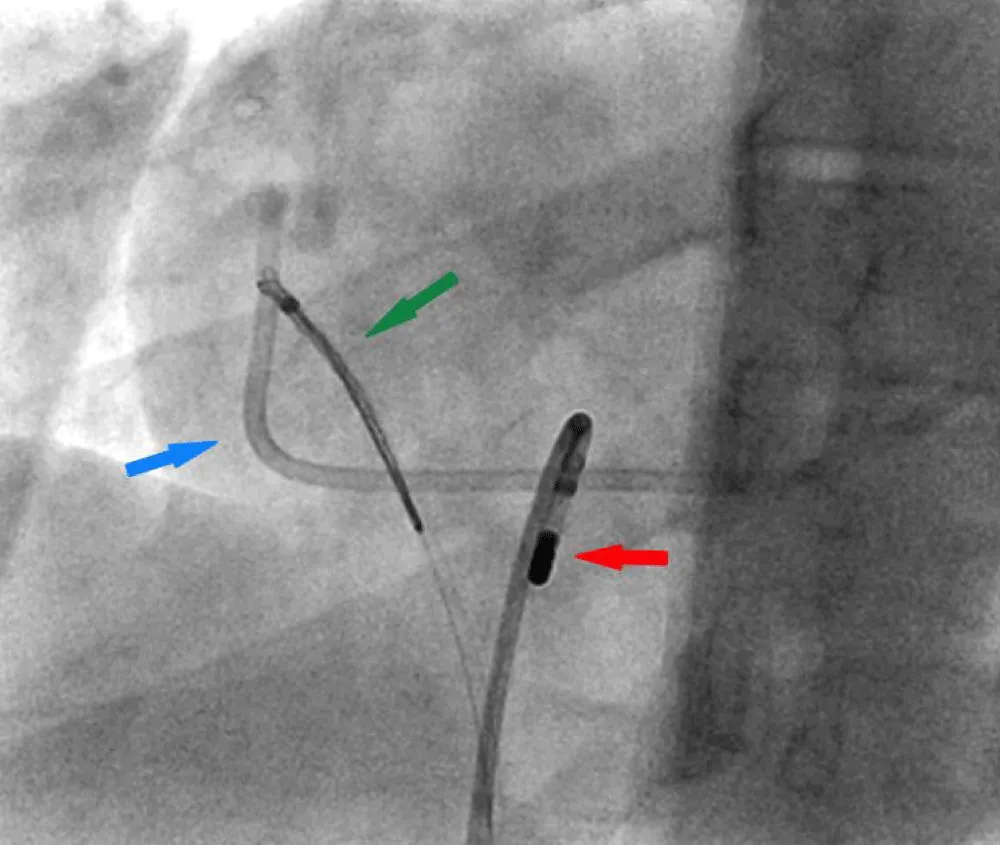

This maneuver freed the right atrial end of the port, for which the endovascular snare was then used with success. The fractured port was finally retrieved as one unit (Figure 4 and Video 2 Click here.

Figure 4: Right Heart catheterization showing Endovascular snare retrieving the freed end of the port. Fractured Port (blue arrow), Navigational steerable catheter (red arrow), Snare (green arrow).